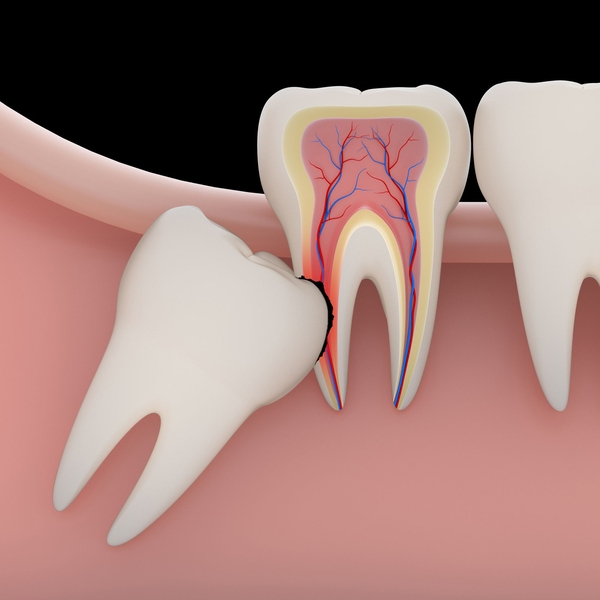

Oral Surgery

As a Fellow of the International Congress of Oral Implantologists, Dr. Polidori can perform numerous types of oral surgery. Before placing implants, he may recommend bone grafting or tori removal to improve your treatment results. He can also perform complex and routine wisdom tooth extraction.